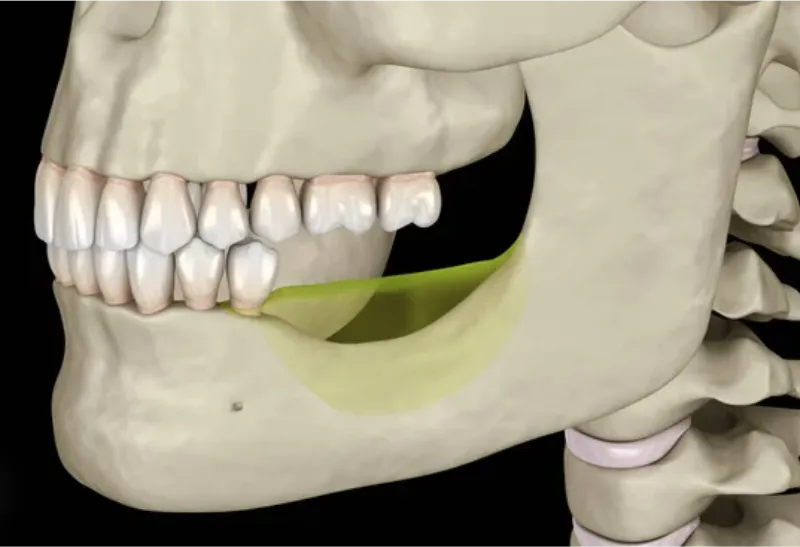

zanik kości

Zanik kości następuje w miejscach, gdzie wcześniej znajdowały się zęby, czyli w obrębie wyrostka zębodołowego szczęki oraz części zębodołowej żuchwy. Po utracie zęba brak naturalnego obciążenia mechanicznego powoduje stopniową resorpcję (wchłanianie) kości. Proces ten może prowadzić do znacznego obniżenia wysokości i objętości kości, co utrudnia późniejsze leczenie protetyczne, np. wszczepienie implantów.